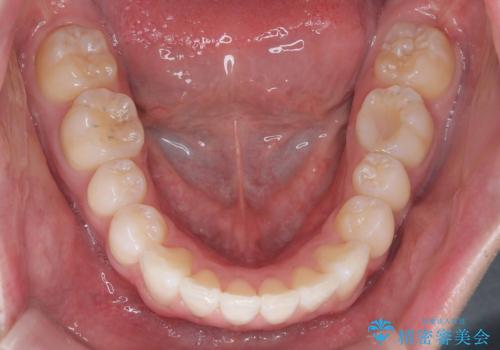

- 「歯のでこぼこを治したい 1年くらいで矯正を終わらせたい」を主訴に来院された患者様です。

叢生量は多く無く歯の傾斜も標準傾斜だったので歯は抜かずにワイヤー矯正で治療を行いました。

左側は2級傾向が強く臼歯の遠心移動をご提案しましたが、1年以内に矯正を終わらせたいという患者様のご意向で希望されず叢生を改善する矯正となりました。